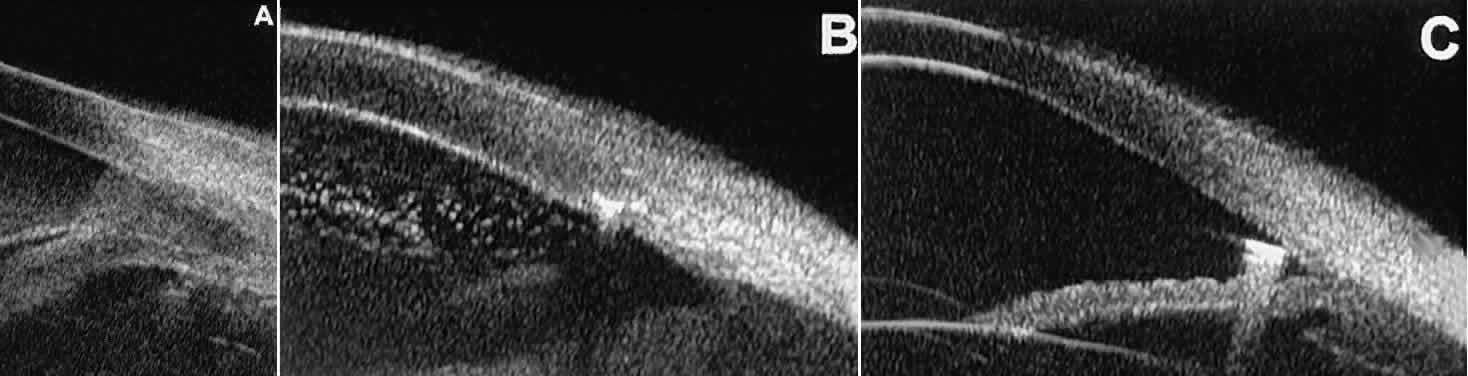

Fig. 21. UBM features of ocular trauma. A. Angle recession with traumatic hyphema after blunt injury. B. Intracorneal foreign body (rose thorn fragment). Note inflammatory cells in adjacent aqueous. C. Intraocular foreign body (glass fragment in inferior angle).

After ocular perforations, lacerations, and intraocular surgery, UBM can show abnormalities such as retained foreign bodies too small to be imaged by other technologies.3,4 Foreign bodies appear on UBM (Fig. 22A and B) as highly reflective focal lesions that are frequently associated with inflammatory features.

Fig. 22. UBM features of primary neuroepithelial cysts of iris and ciliary body. A. Primary neuroepithelial cyst of iris midzone. B. Primary neuroepithelial cyst of iridociliary sulcus. C. Multiple neuroepithelial cysts of peripheral iris and ciliary body. D. Neuroepithelial cysts of pars plana of ciliary body shown in circumferential slice.